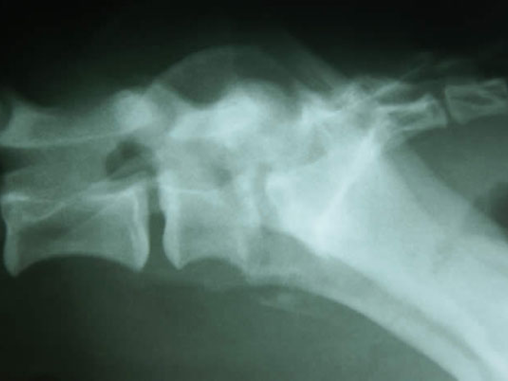

Discospondylitis in a Boxer